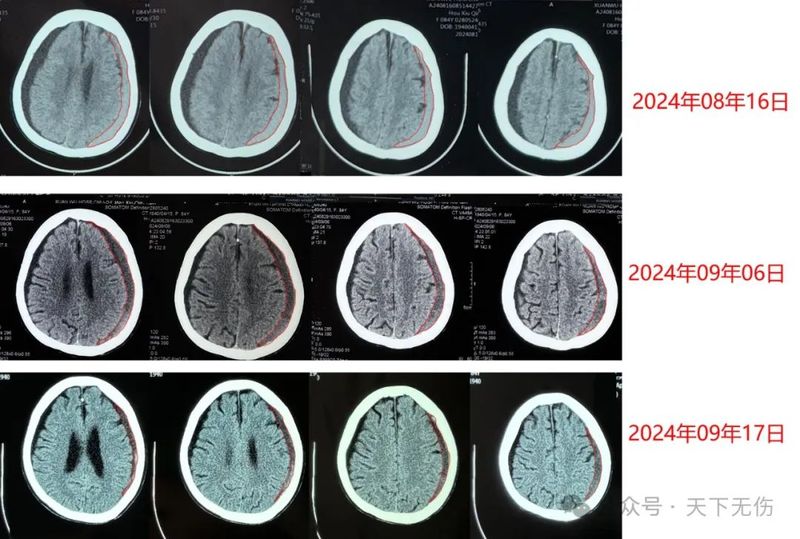

希望我的治療方案盡快普及